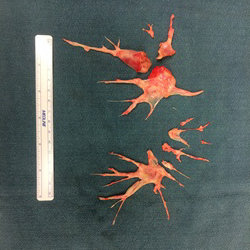

Your surgeon makes incisions in your lung vessels so they can reach the scar tissue. The scar tissue is then removed from the inside of the artery walls on both sides of your lungs.

scar tissue